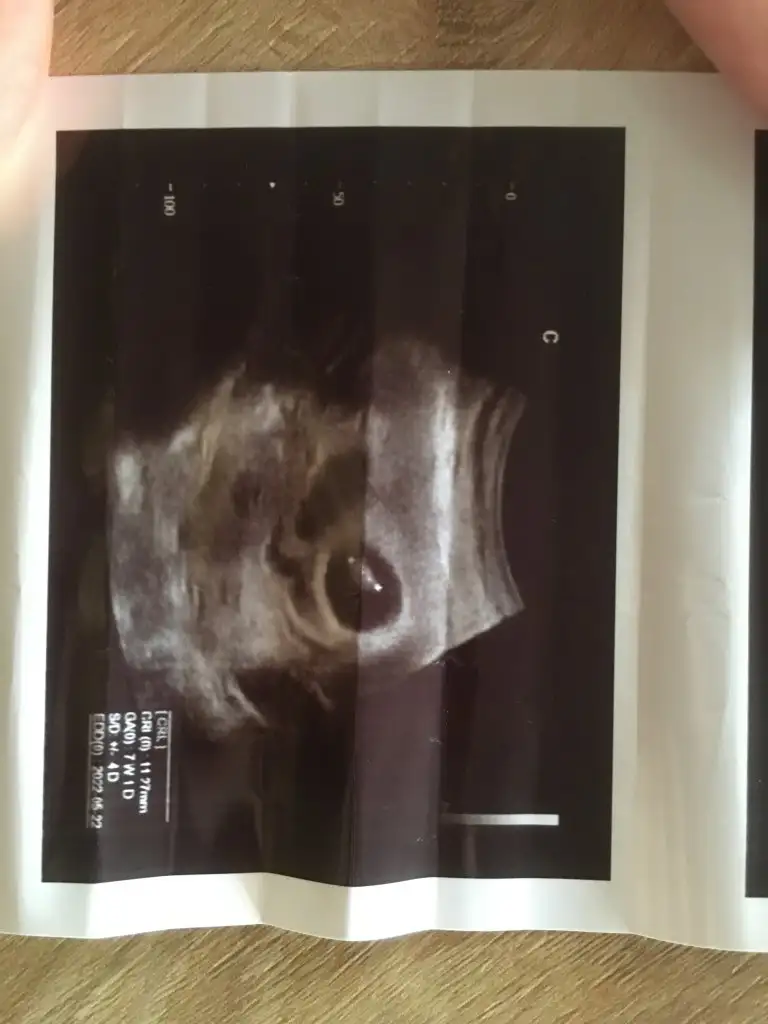

Benm bebeklerimin keseleri de bu şekildeydi ilk ultrasonda biri kiz biri erkek oldu biyerde okumuştum kese yuvarlak olursa kiz fasulye gibi olursa erkek diyeKızlR selam aranızda ikiz cinsiyet tahmini yapabilen varmı bugün bebişleri görmeye gittim

Bende öyle okudum Allahım sağlıklı şekilde kucağımıza alalımda cinsiyettede heycan yapıyor insan sizin kaç haftalık şuandaBenm bebeklerimin keseleri de bu şekildeydi ilk ultrasonda biri kiz biri erkek oldu biyerde okumuştum kese yuvarlak olursa kiz fasulye gibi olursa erkek diye